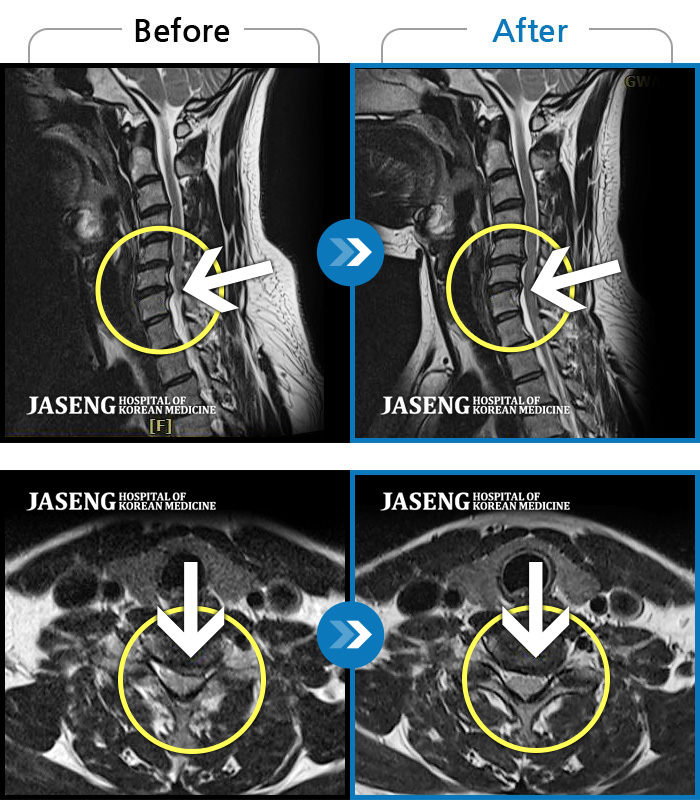

MRI 치료사례

목 통증과 새끼 손가락 저림 및 안정시에도 우측 어깨 통증 호소하여 내원하셨습니다.